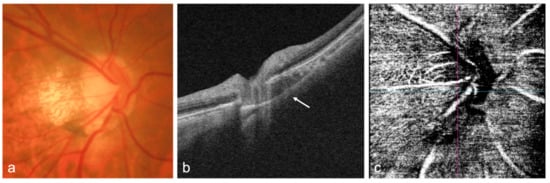

4.3. Optic Nerve

- Kumar, V.; Verma, S.; Azad, S.V.; Chawla, R.; Bhayana, A.A.; Surve, A.; Vohra, R.; Venkatesh, P. Dome-shaped macula—Review of literature. Surv. Ophthalmol. 2021, 66, 560–571. [Google Scholar] [CrossRef] [PubMed]

- Caillaux, V.; Gaucher, D.; Gualino, V.; Massin, P.; Tadayoni, R.; Gaudric, A. Morphologic characterization of dome-shaped macula in myopic eyes with serous macular detachment. Am. J. Ophthalmol. 2013, 156, 958–967.e1. [Google Scholar] [CrossRef] [PubMed]

- Dai, F.; Li, S.; Wang, Y.; Li, S.; Han, J.; Li, M.; Zhang, Z.; Jin, X.; Dou, S. Correlation between posterior staphyloma and dome-shaped macula in high myopic eyes. Retina 2020, 40, 2119–2126. [Google Scholar] [CrossRef]

- Ohsugi, H.; Ikuno, Y.; Oshima, K.; Yamauchi, T.; Tabuchi, H. Morphologic characteristics of macular complications of a dome-shaped macula determined by swept-source optical coherence tomography. Am. J. Ophthalmol. 2014, 158, 162–170.e1. [Google Scholar] [CrossRef]

- Ellabban, A.A.; Tsujikawa, A.; Matsumoto, A.; Yamashiro, K.; Oishi, A.; Ooto, S.; Nakata, I.; Akagi-Kurashige, Y.; Miyake, M.; Elnahas, H.S. Three-dimensional tomographic features of dome-shaped macula by swept-source optical coherence tomography. Am. J. Ophthalmol. 2013, 155, 320–328.e2. [Google Scholar] [CrossRef] [PubMed] [Green Version]